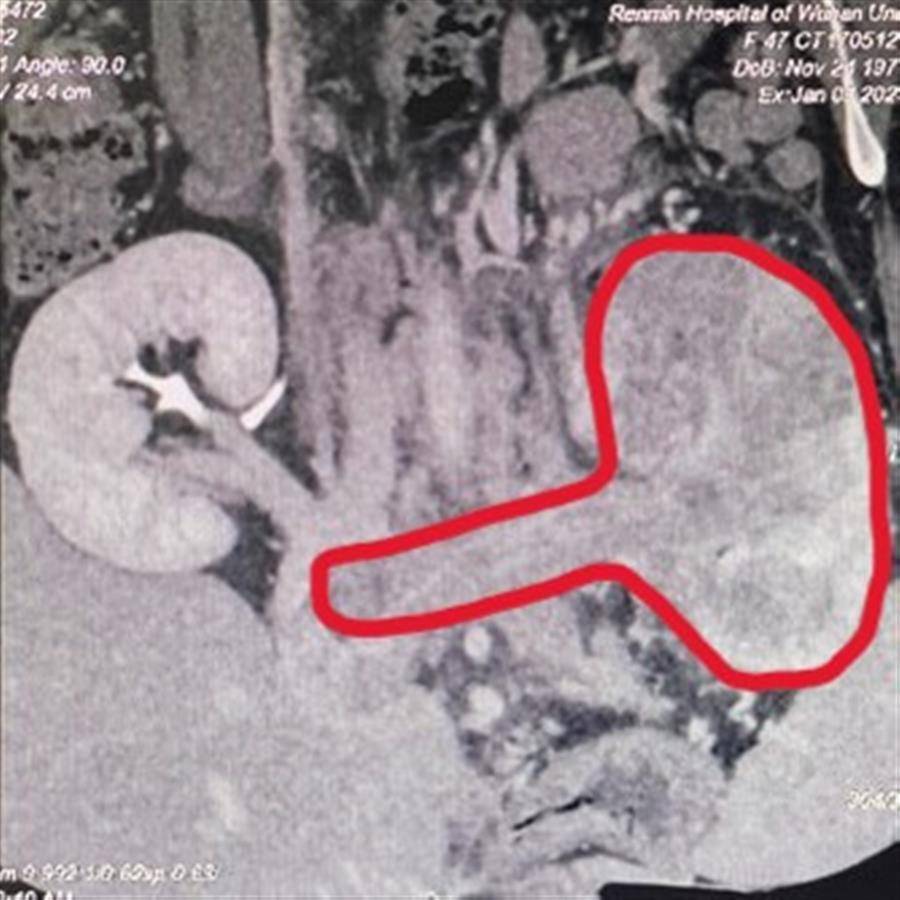

1月下旬,2位患者几乎同时到该院泌尿外I科求助。一位是年仅18岁的小伙小张,因身体不适在湖北某县医院检查时,查出左肾有一个17.5厘米X14.3厘米X16.8厘米的巨大实质性占位性肿块。另一位是47岁的陶姓女士,她在体检时发现左肾巨大实质性占位性病变,并伴随腔静脉癌栓形成,穿刺活检病理证实还有上皮样血管及脂肪瘤,进一步完善检查发现癌栓已进入下腔静脉,并达到MayoII级。